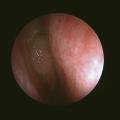

Polypose nasosinusienne

La polypose nasosinusienne est une rhinosinusite diffuse caractérisée par la présence de polypes bilatéraux dans les cavités nasales venant du massif ethmoïdal. Sa physiopathologie repose sur une inflammation chronique de la muqueuse des cavités nasales et sinusiennes marquée par une infiltration éosinophilique plus ou moins…

Tableaux et figures